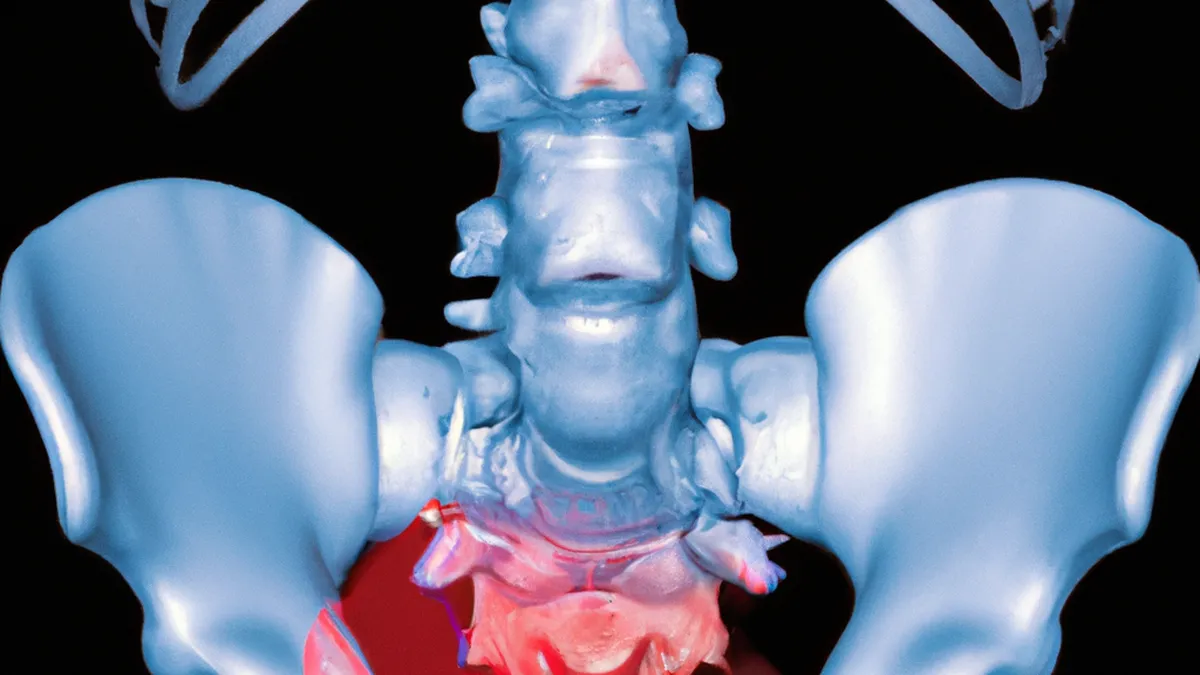

The sacroiliac (SI) joint connects the lower spine to the pelvis. It transfers weight from the upper body to the lower limbs during walking, running, and standing. Inflammation, misalignment, or dysfunction of the SI joint leads to sacroiliac joint dysfunction. Individuals often experience sharp, stabbing pain in the lower back and buttocks, which may radiate down the legs.